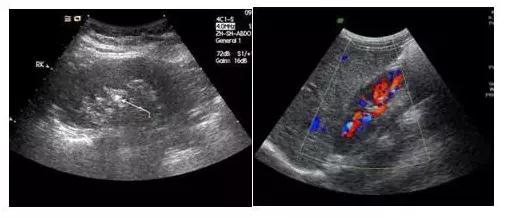

首先,黑白超和彩超并不是在影像的顏色上有區(qū)別,許多人認(rèn)為彩超和黑白超的區(qū)別就是彩色電視機(jī)和黑白電視機(jī)的區(qū)別,其實(shí)不然,彩超顯示的圖像也是黑白的。

它們的區(qū)別是黑白超用灰度調(diào)制顯示聲束掃描人體切面的聲像圖;彩超則是在黑白超的基礎(chǔ)上,增加了血流信號(hào)的處理,一般用紅、藍(lán)、綠三種基本顏色,呈現(xiàn)出檢查區(qū)域的血管分布、血流方向、血流速度等